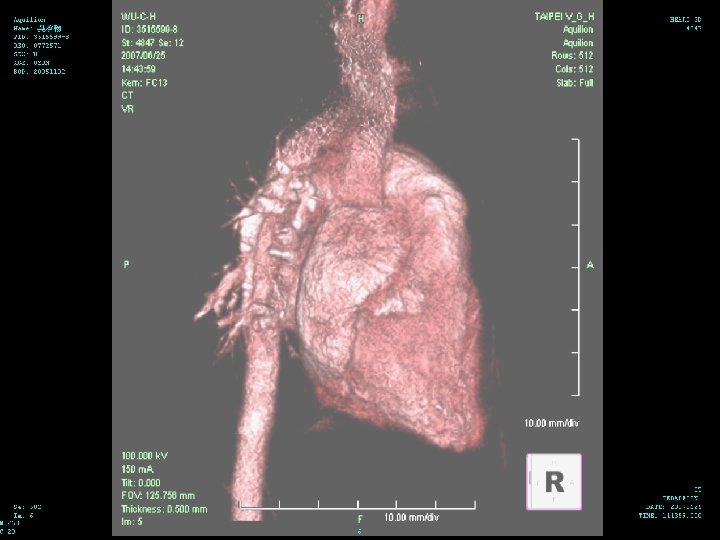

Hospital Course (6/25 -28) 3 D CT of chest performed on 6/25 n There is narrowing of the trachea in the level of aortic arch with narrowest diameter about 0. 25 cm about 1. 2 cm in length n There is dextrocardia with left side aortic arch n There is double SVC with left SVC drainage to coronary sinus n